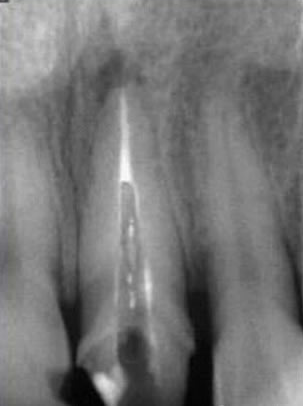

大多數(shù)醫(yī)生在樁道預備時習慣于干燥預備根管(圖 1),這樣很容易破壞根管壁的牙本質(zhì)結(jié)構(gòu),同時也可形成較厚的玷污層,影響樹脂水門汀與牙體組織的粘接。因此,臨床操作時應選擇沖洗的方法冷卻預備根管(圖 2),防止牙膠及封閉劑粘連附著于根管壁形成第二玷污層(根管治療時形成的玷污層稱為第一玷污層),有利于樹脂水門汀與根管牙本質(zhì)的粘接。

圖1:干燥預備根管。 圖2:沖洗預備根管。